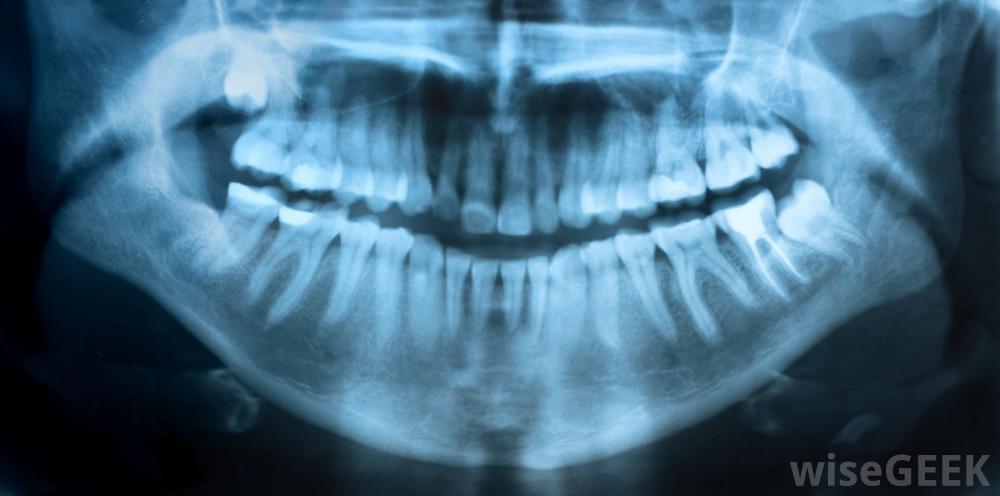

流动牙医经常携带进行牙科x光检查所需的设备。

由于高质量的牙科护理需要使用一系列设备、牙科制剂和药物,因此移动牙科服务通常乘坐一辆面包车或卡车,配备齐全所需的工具护理。虽然此类车辆中的设备通常取决于服务计划提供的护理类型,但这些货车和卡车通常包括进行牙科检查、填充空洞、涂抹牙科密封剂、清洁患者牙齿所需的x光设备和工具,一些移动牙科车甚至配备了拔牙设备。